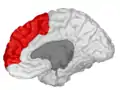

Position of superior frontal gyrus (shown in red)